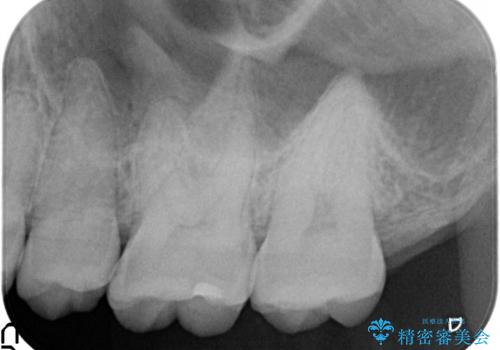

虫歯の再発リスクを減らすセラミックインレー

- 他院でインビザラインの治療中に虫歯を発見されたため、治療を希望され来院された患者様です。

セラミックインレーにて治療を行いました。

セラミックインレーは適合が良く、虫歯の再発リスクを減らすことができます。